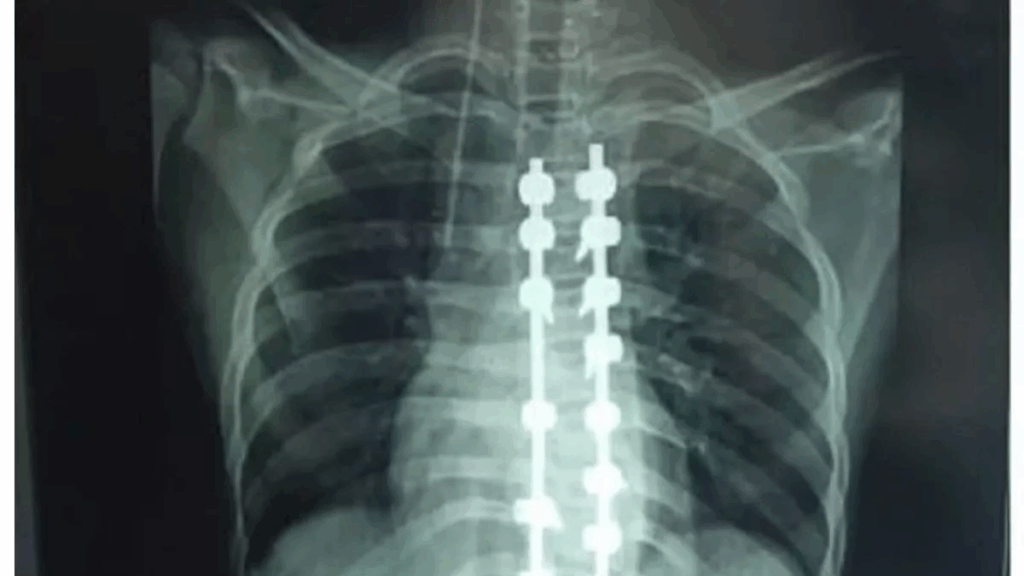

प्रयागराज, दुर्घटना अथवा अन्य कारणों से जिनकी हड्डियां टूट जाती हैं और इलाज में रिंग फिक्सेटर या लिंब रिकन्सट्रक्शन डिवाइस का इस्तेमाल किया जाता है, उन्हें जांच के लिए अब बार-बार एक्सरे कराने की जरूरत नहीं पड़ेगी। सेंसर बता देगा कि हड्डी कितनी जुड़ गई है।

मोतीलाल नेहरू राष्ट्रीय प्रौद्योगिकी संस्थान (एमएनएनआईटी), प्रयागराज और किंग जॉर्ज मेडिकल यूनिवर्सिटी (केजीएमयू), लखनऊ के विज्ञानियों ने मिलकर इसके लिए एक अत्याधुनिक सेंसिंग डिवाइस विकसित की है। इससे एक्सरे पर होने वाले खर्च के साथ ही रेडिएशन के दुष्प्रभावों से भी राहत मिलेगी। इस डिवाइस का परीक्षण प्रयोगशाला स्तर पर सफलतापूर्वक पूरा कर लिया गया है। अब इसे मरीजों पर आजमाने की तैयारी की जा रही है। शोधकर्ताओं ने डिवाइस के पेटेंट के लिए आवेदन भी कर दिया है।

सर्जरी के समय ही यह सेंसर हड्डी जोड़ने वाली रॉड या फिक्सेटर पर लगाया जाएगा, जो समय-समय पर यह जानकारी देगा कि हड्डी की स्थिति क्या है। यह सेंसर ऑप्टिकल फाइबर तकनीक पर आधारित है, जो पूरी तरह से इलेक्ट्रिकल रूप से निष्क्रिय होता है और शरीर में किसी भी प्रकार की प्रतिक्रिया नहीं करता। इस सेंसर की सबसे खास बात यह है कि इसे कृत्रिम बुद्धिमत्ता (एआई) और रियल टाइम डेटा ट्रांसमिशन से सुसज्जित किया गया है। यानी डाक्टर को किसी भी समय, कहीं से भी मरीज की हड्डी जुड़ने की सटीक जानकारी प्राप्त हो सकेगी। इससे मरीज को बार-बार अस्पताल जाने की आवश्यकता भी नहीं होगी।

मुख्य अनुसंधानकर्ता डाॅ. अभिषेक तिवारी ने बताया कि लगभग दो वर्षों के प्रयास के बाद सेंसिंग डिवाइस को प्रयोगशाला स्तर पर विकसित कर उसका परीक्षण भी सफलतापूर्वक पूरा किया जा चुका है। अब इसे केजीएमयू के सहयोग से क्लीनिकल ट्रायल के चरण में लाया जा रहा है, जहां वास्तविक मरीजों पर इसका परीक्षण किया जाएगा। सेंसर डॉक्टर को यह बताने में मदद करेगा कि फिक्सेटर कब हटाना है और कब नहीं।